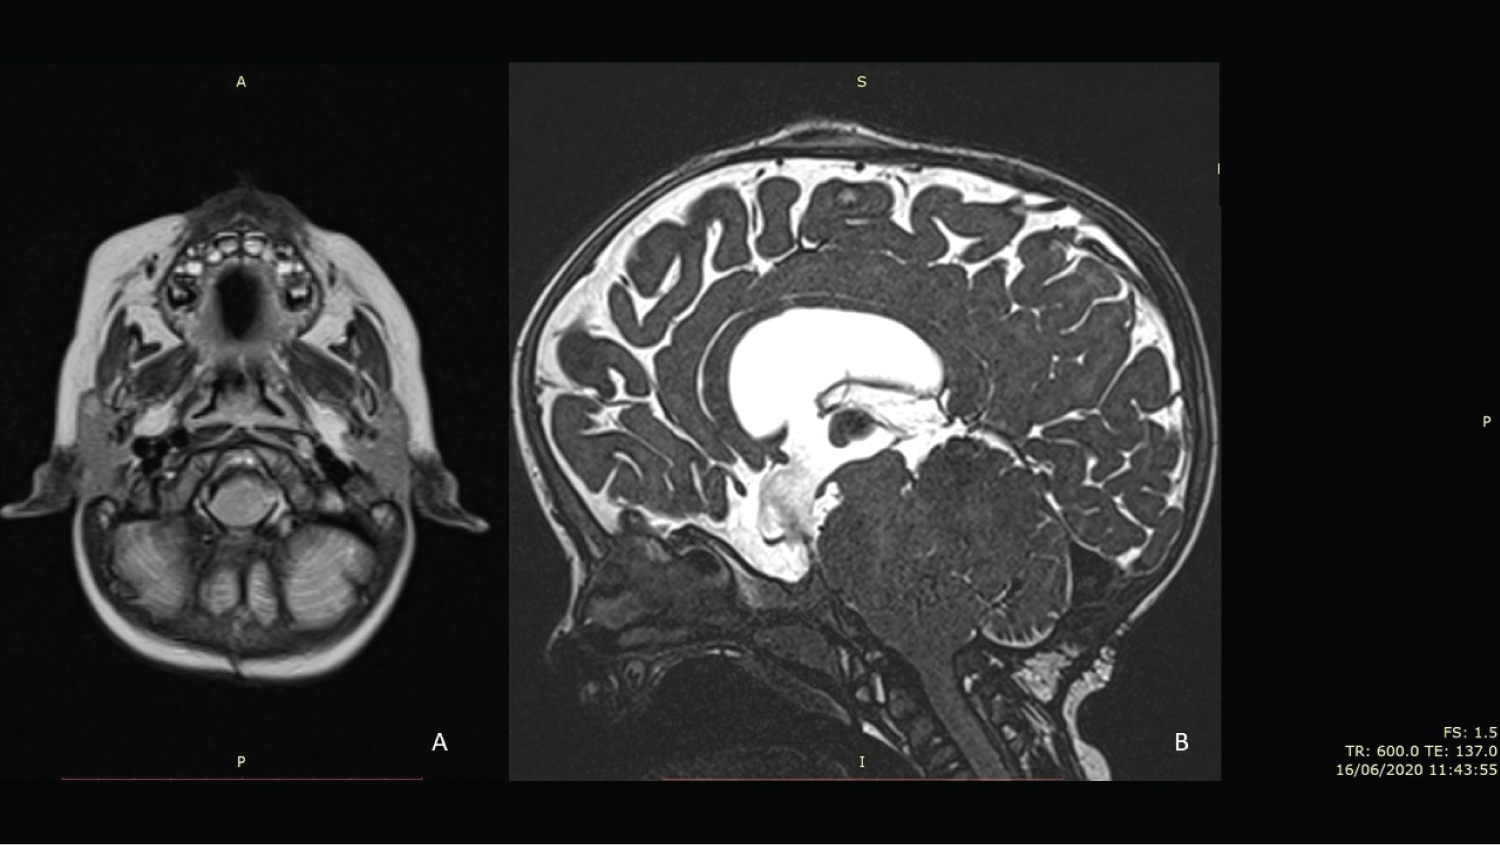

Craniocervical junction MRI with CSF flow study confirmed medullary compression with impaired CSF flow at the foramen magnum without T2 medullary hyperintensity. Craniovertebral decompressive surgery was performed - C1 laminectomy, posterior fossa craniectomy of approximately 2 × 2 centimetres and extensive release of fibrotic bands on the posterior atlanto-occipital membrane with dural expansion. Intraoperative ultrasound imaging with doppler showed adequate decompression of the cervicomedullary transition and an improvement in CSF flow velocities and hence no duraplasty was required. Multimodal intraoperative neuromonitoring was used to maximize surgical safety. The postoperative period was uneventful. During the 6 months of postoperative follow-up, the infant improved cephalic control and a boost in motor development has been observed. Follow up MRI is illustrated in Figure 6.

Figure 6: A) MRI T2 axial sequence trough foramen magnum revealing cervicomedullary decompression; B) MRI T2 Sagittal Constructive Interference in Steady State sequence revealing a C1 laminectomy and a suboccipital craniotomy decompressing the cervicomedullary transition. CSF flow through III ventricle ventriculocisternostomy can be appreciated. View Figure 6